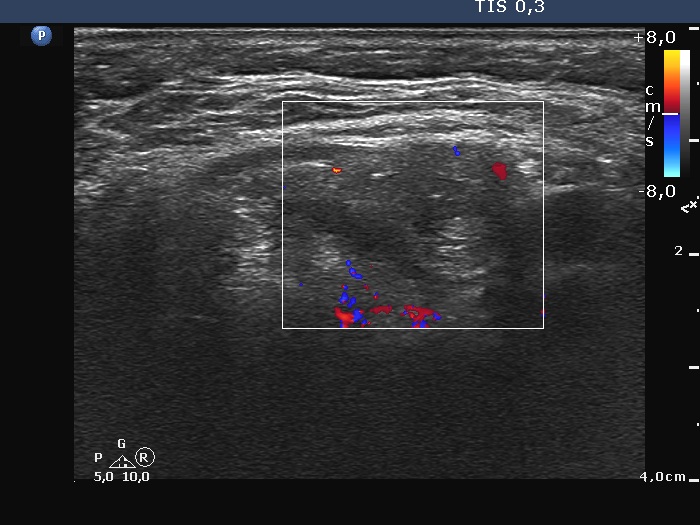

Lymph nodes - case 1602 (ultrasonographic picture 10)

Left side of the neck, 7 cm above the thyroid, longitudinal scan, color Doppler mode. The vascularity is although scanty but present.